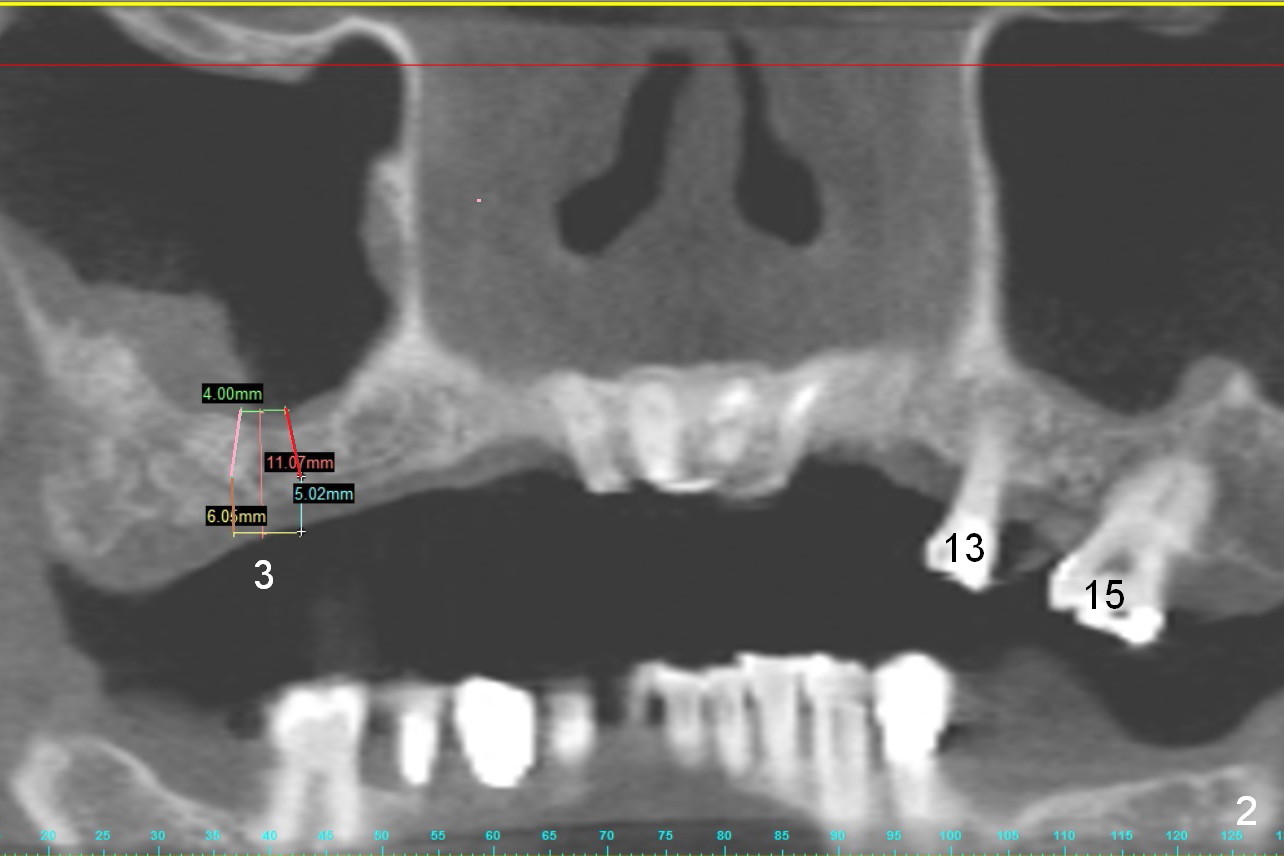

A 68-year-old lady has several missing teeth (Fig.1,2). She has agreed to have an implant at the site of #3 (Fig.3) to stabilize an upper removable partial denture (RPD). The latter will be more stable if an extra implant is placed at #6 (Fig.1,2,6). There is enough bone to place implants at #4,5 (Fig.4,5). Bone density at these sites is low. Osteotomy should be underprep with bone condensation. Edentulous space is high so long abutments are required (9 mm instead of 3 or 5 mm (regularly used)). Angled abutments should be prepared.